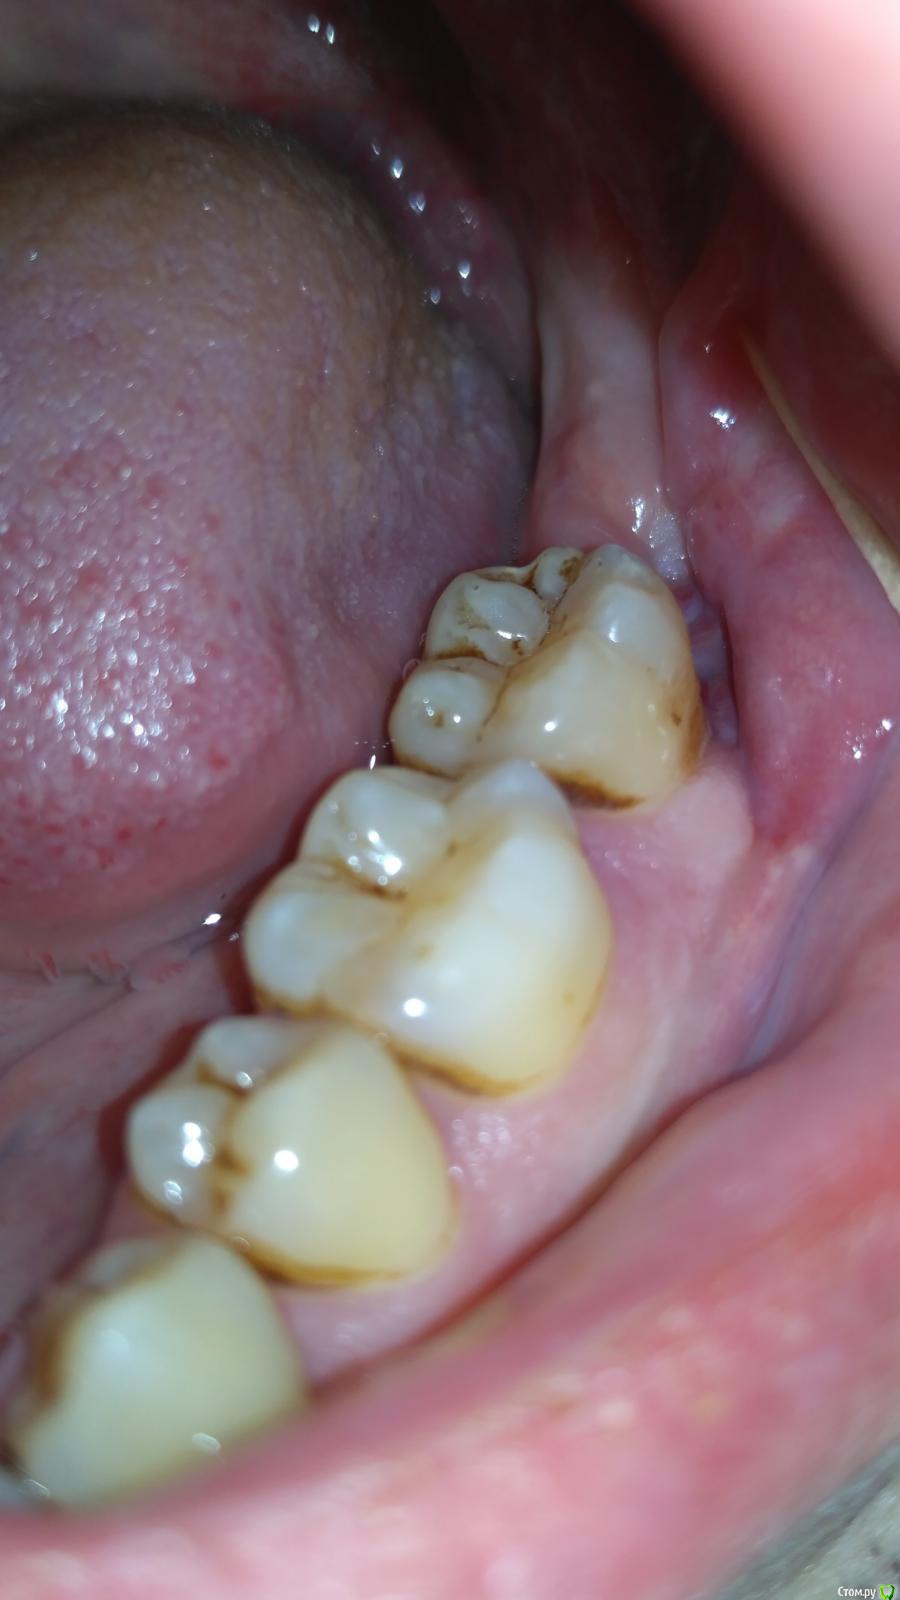

medbratec Опубликовано 10 октября, 2016 Автор Поделиться Опубликовано 10 октября, 2016 Пока полоскаю травами, на ночь Метрогил Дента. Стало меньше температурить.Завтра поеду на консультацию в отделение челюстно-лицевой хирургии.Как и обещал прикрепляю несколько фоток: Ссылка на комментарий

medbratec Опубликовано 13 октября, 2016 Автор Поделиться Опубликовано 13 октября, 2016 Я вас прекрасно понимаю. Был бы специалистом, то так сразу и сделал. Просто не знаю, что конкретно и под каким углом показывать. Сделал несколько скриншотов. Напишите, если они окажутся не слишком информативны. Ссылка на комментарий

medbratec Опубликовано 13 октября, 2016 Автор Поделиться Опубликовано 13 октября, 2016 Ссылка на комментарий